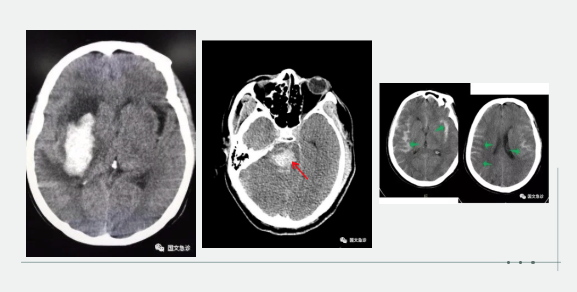

突發(fā)意識(shí)不清兩小時(shí)入院。據(jù)家屬描述“發(fā)現(xiàn)的時(shí)候老爺子躺在地上叫了好幾聲也沒(méi)有反應(yīng),上去推了推也沒(méi)動(dòng)靜趕忙就打120了。根據(jù)該家屬的描述,緊急為患者進(jìn)行查體:該患者意識(shí)成昏迷狀態(tài),查體不合作,雙側(cè)瞳孔等大等圓,呼吸間斷 血壓237/115mmhg。內(nèi)科醫(yī)生進(jìn)一步向家屬了解患者既往血壓情況,該家屬表示:“血壓一直都很高,降壓藥也不按時(shí)吃就難受的時(shí)候吃一片”。進(jìn)一步考慮患者腦內(nèi)出血,立即行頭部CT。為患者打開(kāi)急診綠色通道“遵循檢查或繳費(fèi)的原則”。CT結(jié)果顯示患者左側(cè)大腦半球出血、小腦出血、腦室積血。醫(yī)生立即向家屬交代病情,該家屬哽咽著說(shuō):“你說(shuō)這早上剛還一起吃團(tuán)圓飯呢,一轉(zhuǎn)身的工夫,老爺子就倒地不起了。醫(yī)生您說(shuō)啊,好好的一個(gè)人怎么就腦出血了?以前除了血壓高一點(diǎn)癥狀都沒(méi)有呀!”

突發(fā)意識(shí)不清,1小時(shí)入院。該妻子滿(mǎn)眼淚水地向醫(yī)生訴說(shuō):“我們剛吃完飯,他說(shuō)困了睡一會(huì)兒,這怎么突然就叫不醒了呢?醫(yī)生您快看看,這是咋了呀?”“李先生平時(shí)身體怎么樣?”“我家老李平時(shí)身體可好了,你別看他長(zhǎng)得胖,一年感冒的次數(shù)都少。對(duì)了,就是血壓有點(diǎn)高?!备鶕?jù)家屬描述,立即為患者查體:該患者呈深度昏迷狀態(tài),雙側(cè)瞳孔不等大 左側(cè)3.5mm、右側(cè)5.0mm,血壓250/190,雙側(cè)病理征陽(yáng)性。初步考慮患者腦內(nèi)出血,急行頭部CT檢查。結(jié)果示:右側(cè)小腦及腦干不規(guī)則高密度灶破入腦室,三腦室及四腦室內(nèi)見(jiàn)高密度灶。患者病情危重醫(yī)生立即為患者辦理入院,急忙送往ICU(重癥監(jiān)護(hù)室)進(jìn)行進(jìn)一步治療。